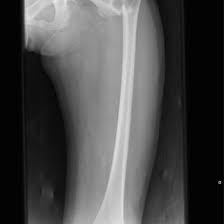

X-ray Left Femur AP/Lateral

An X-ray Left Femur AP/Lateral is a diagnostic imaging test that captures detailed front (anteroposterior) and side (lateral) views of the left thigh bone (femur). It helps doctors evaluate the bone’s structure to detect fractures, infections, tumors, or other abnormalities.

This scan helps doctors examine the femur for fractures, infections, tumors, or other bone-related conditions.

An X-ray Left Femur AP/Lateral can detect fractures, infections, tumors, and other abnormalities in the thigh bone. It provides detailed images from both front and side views to help doctors diagnose and plan treatment effectively.